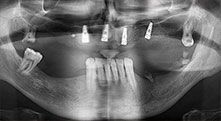

dentatura residua

Un paziente di 40 anni con una dentatura residua limitata desiderava un restauro basato su impianto. Dal momento che è un fumatore, era controindicato un rialzo del seno mascellare con una protesi fissa. È stata quindi programmata una protesi a barre.

Piezomed B6

La cresta alveolare è stata incisa su entrambi i lati tramite piezochirurgia (strumento utilizzato: Piezomed B6). Gli impianti sono stati posizionati con la stessa procedura e l'osso peri-implantare è stato costruito con la tecnica GBR.

impianti

I quattro impianti sono fissati come programmato. I molari mascellari distali possono comunque essere utilizzati per fissare la protesi in linea introdotta un mese dopo l'impianto.